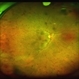

- Andrea E. Arriola-López MD MSc

Fundus camera

OPTOS Dakota - Description

- 56-year-old man, BCVA 20/25. Incidental finding. Laser was given.